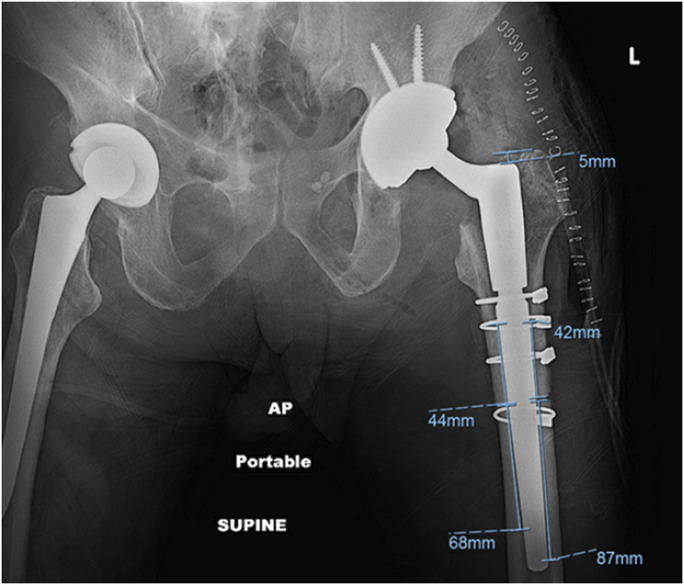

Methods: This is a single-center retrospective cohort study of a prospectively collected database including all patients who received a TSTS from 2016 to 2020. Data collected include surgery type, presence of an ETO, and stem specifications. Radiographs were reviewed to analyze cortical contact and postoperative subsidence. Pearson's correlation coefficient was used to determine the association between contact length and subsidence.

Results: This cohort consisted of 299 hips, and 66 hips necessitated an ETO at the time of TSTS. Patients who required an ETO were more likely to subside (2.5 ± 0.2 mm vs 5.0 ± 0.7 mm, p < 0.001) and were more likely to subside >5 mm (32.3% vs 14.5%, p = 0.001). After controlling for other variables, an ETO was an independent risk factor for significant subsidence (adjusted OR: 3.4, p = 0.02). Contact length below the ETO was inversely related to stem subsidence (correlation coefficient of -0.26; p = 0.037), and multivariable logistic regression demonstrated bicortical contact > 30 mm to be a protective factor for significant subsidence (adjusted OR: 0.12, p < 0.001). Patients who received an ETO had a higher aseptic rerevision rate than patients who had a TSTS implanted without an ETO (16.1% vs 6.6%, p = 0.018).

Clinical relevance: An extended trochanteric osteotomy is an excellent technique to gain direct visualization of the femoral canal. However, it is not without its associated morbidity and postoperative complications, specifically stem subsidence. The results of this study suggest that when preparing for a TSTS after an ETO, careful consideration should be taken to confirm 3 cm of cortical engagement below the transverse limb of the ETO. The scaffolding technique, which prioritizes stem preparation followed by ETO closure, facilitates achieving sufficient cortical contact in the intact canal below the ETO segment. Consideration for intraoperative radiographs to confirm appropriate contact length and location may ensure sufficient fixation that will minimize the risk of postoperative stem subsidence.